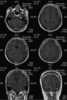

Multiple abscesses